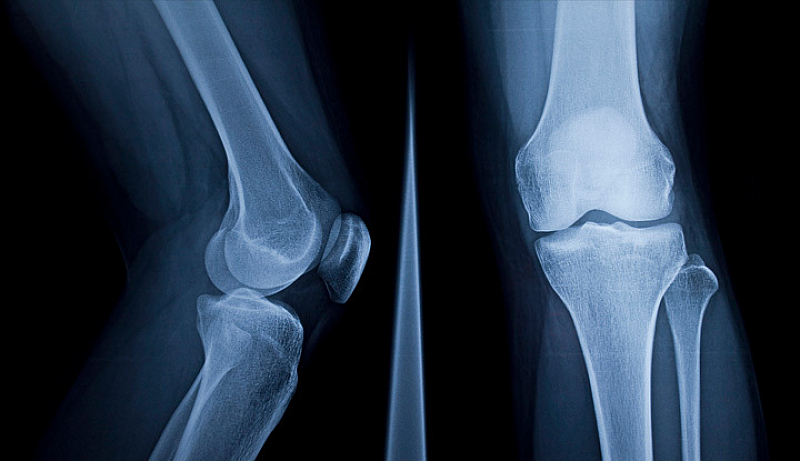

Система с изкуствен интелект, която може да прогнозира как ще изглежда рентгенова снимка на коляното в бъдеще, би могла да промени начина, по който се лекуват милиони пациенти с остеоартрит, пише BBC.

Остеоартритът е дегенеративно ставно заболяване, засягащо повече от 500 милиона души по света, според университета. Той е водещата причина за инвалидност при възрастните хора.

Системата с изкуствен интелект е била обучена върху близо 50 000 рентгенови снимки на почти 5000 пациенти – един от най-големите набори от данни за остеоартрит в света.